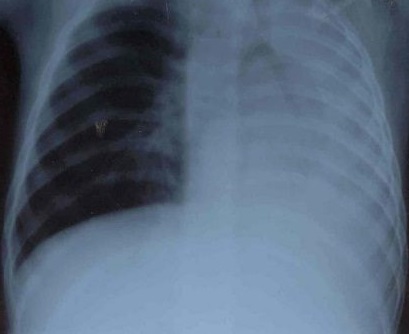

На рентгеновских снимках выявляют следующие признаки, указывающие на спадение легочной ткани:

Однородное затемнение в области поражения. Размеры тени зависят от вида ателектаза: при долевом выявляется обширное затемнение, при сегментарном — в виде клина или треугольника, расположенного вершиной к корню легкого, дольковые ателектазы множественные и похожи на очаговую пневмонию. Дистензионный ателектаз расположен низко, около диафрагмы, имеет небольшие размеры и вид поперечных полос или темных дисков. Смещение органов: при компрессионном ателектазе смещение наблюдается в здоровую сторону, так как на стороне поражения давление больше, при обтурационном, наоборот – смещение будет в сторону ателектаза, так как на стороне поражения нарастает притягивающее отрицательное давление. Подъем купола диафрагмы – это видно по расположению печени.

Помимо всего перечисленного выше, рентгеноскопия, то есть исследование «вживую», позволяет увидеть куда смещаются органы в зависимости от фазы дыхания, кашля. Это является дополнительным признаком ателектаза, помогающим выявить тип болезни.

Больной жалуется на одышку. Кожные покровы его бледны; со стороны видимых слизистых может отмечаться синюшность. При аускультации (прослушивании) легких шум дыхания либо ослаблен, либо отсутствует. За счет уменьшения объема легкого при большом ателектазе может быть смещено в сторону поражения средостение; также на стороне поражения может быть высокое стояние диафрагмы. Диагноз подтверждается рентгенологически. Поскольку в закрытом пространстве альвеол присутствуют и развиваются микробы, ателектаз часто осложняется пневмонией.